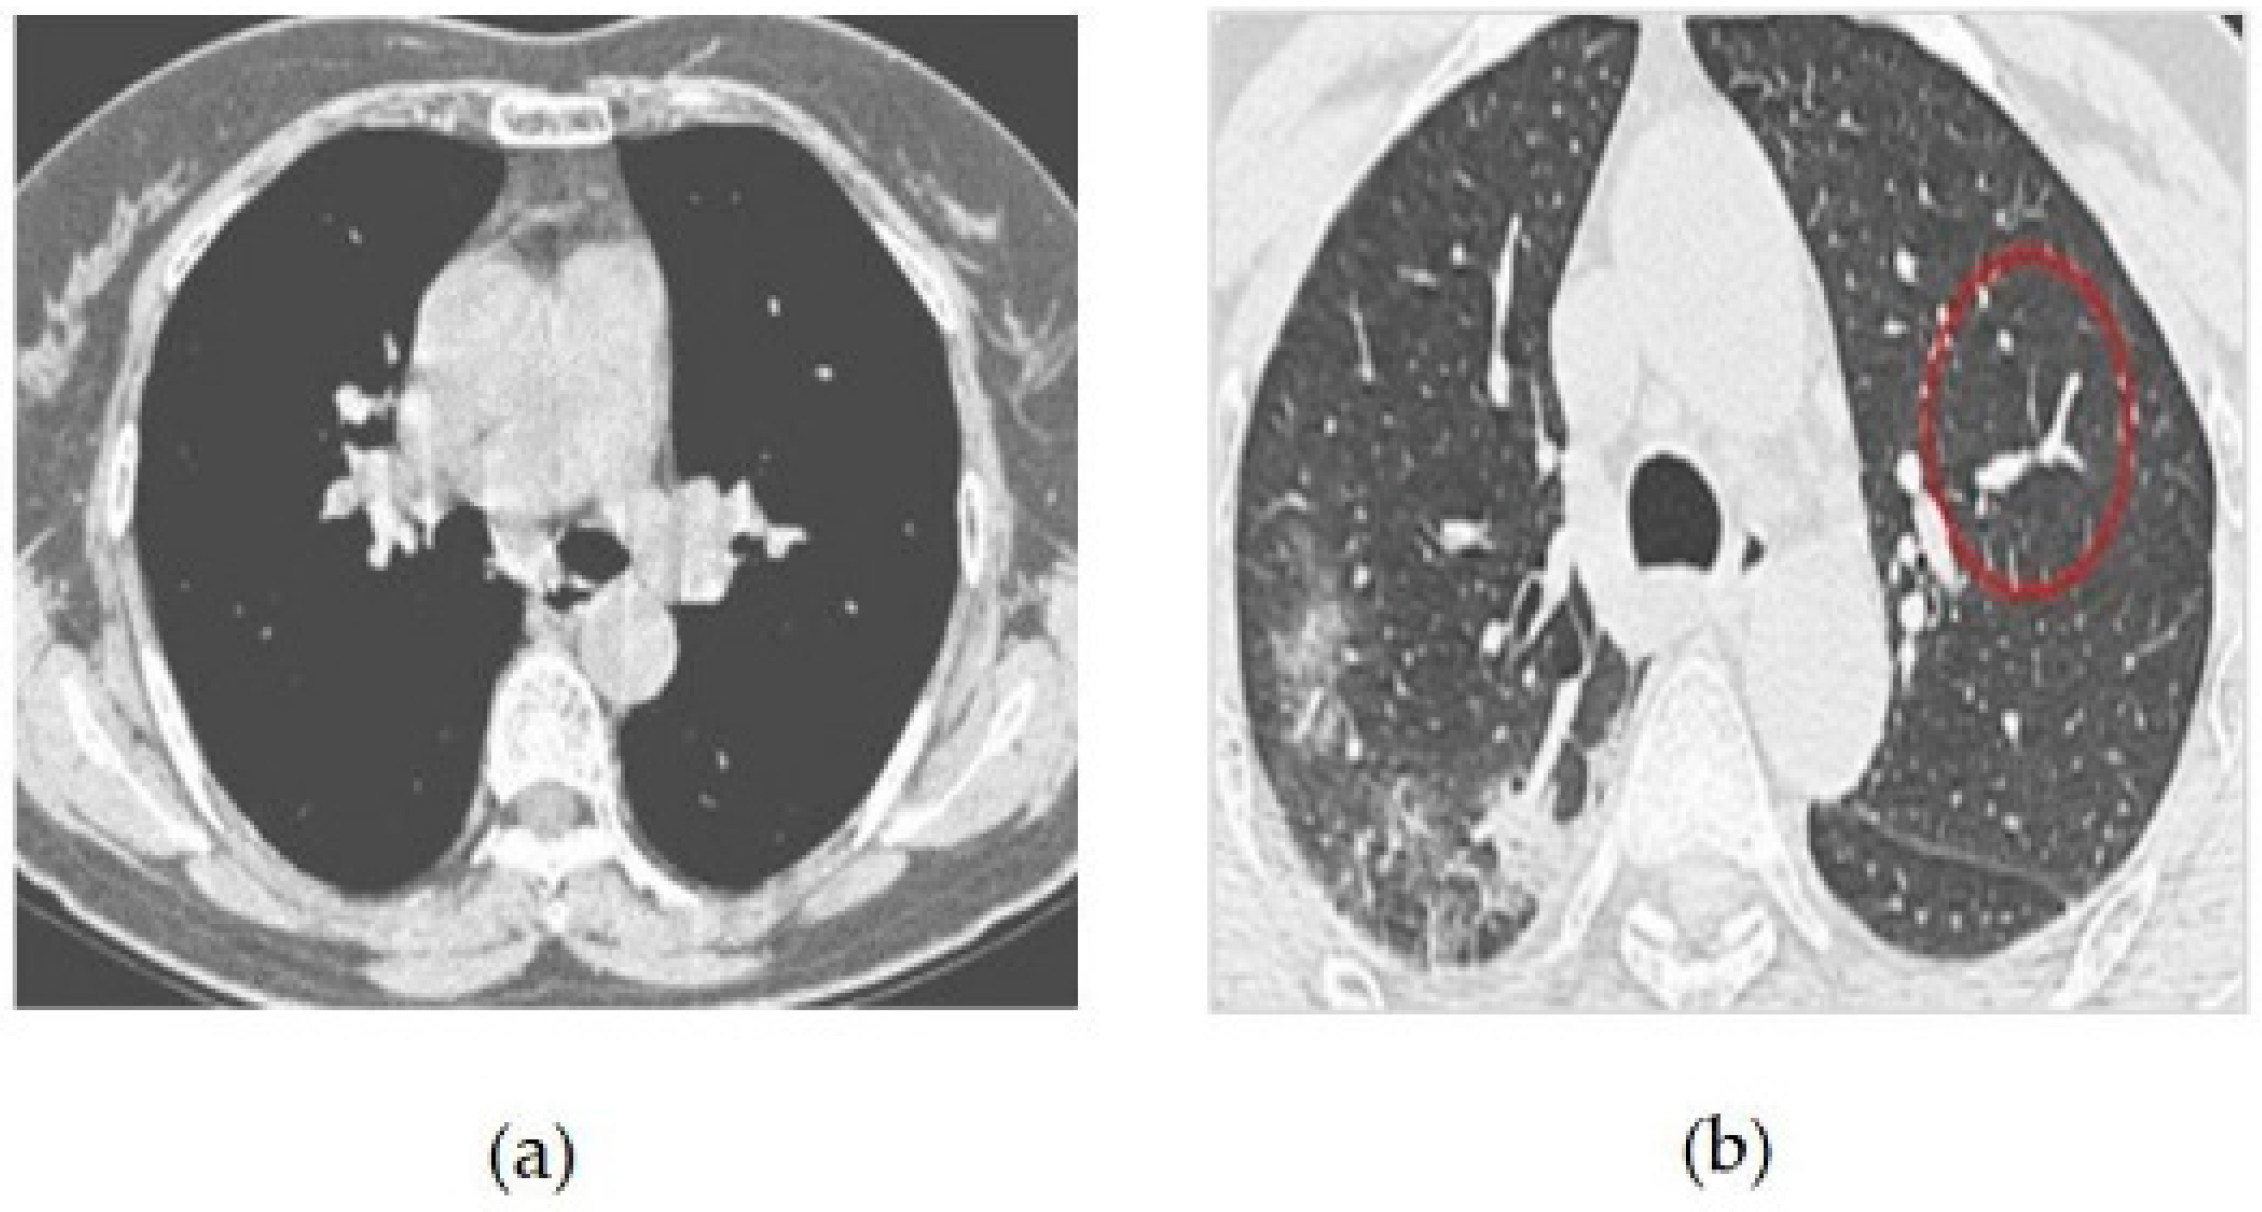

The CT image dataset contains approximately 349 CT images from 216 patients with coronavirus and 397 patients without coronavirus. The images were collected from hospitals that treat both coronavirus and non-coronavirus patients, but only the positive and negative cases for coronavirus were included in the dataset [13,14]. Some of the samples of coronavirus images in both positive and negative classes are given in Figure 4. The features of the dataset are as follows:

Figure 5 CT scans, or computed tomography scans, use X-rays to create detailed images of the inside of the body. CT scans can be helpful in diagnosing respiratory illnesses such as SARS-CoV-2, the virus that causes COVID-19. CT scans can show the presence of lung abnormalities such as ground-glass opacities and consolidation, which can be indicative of viral pneumonia.

Figure 4. (a) COVID-19 Negative (COVID-19 images collection dataset) (b) COVID-19 Positive (COVID-19 images collection dataset).

Figure 5. (a) Patient healthy image, (b) Patient with pneumonia, and (c) Patient with +Ve COVID-19 images COVID-19 negative.